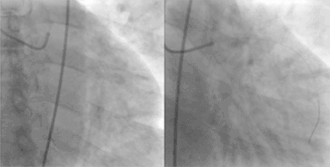

![]() Showing the coronary arteries that are subject to narrowing - resulting in reduced blood supply to the cardiac muscle. | |